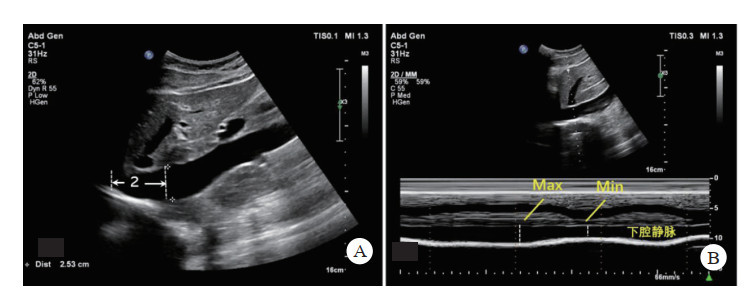

2.6 容量评估快速超声休克检查(rapid ultrasound in shock, RUSH)是迅速地系统性排查一些特殊低血压病因的超声检查方法,可用于鉴别病情不稳定或原因不明的低血压的病因学诊断。其核心理念在于对“泵、容量、管道”三个系统的快速检查,“泵”指心脏,心排量、心功能情况,“容量”指容量大小,容量不足或容量负荷大,“管道”指血管,血管是否结构正常完整。RUSH最早始于急诊休克抢救中的快速病因诊断及鉴别诊断,但近几年已开始同样用于直升机平台的急救体系[45]。对于容量的评估,除了上述提及E-FAST检查中对心脏结构、心包积液、胸腔、腹腔积液的探查外,还应包括通过下腔静脉(inferior vena cava, IVC)的充盈程度对全身容量进行评估。

下腔静脉检查常用IVC塌陷率,也称下腔静脉呼吸变异指数(shape change index, SCI),是反映右心房压力的敏感指标。当血容量不足时,IVC塌陷明显增加,当血容量过高时,IVC塌陷率明显减少[46]。

创伤患者的低血压的常见原因是出血引起的低血容量,还包括当心脏或中枢神经系统发生冲击创伤时,可能引起心源性休克,创伤造成的剧烈疼痛也可能引起神经源性休克,而超声对IVC的快速测量可以间接估测中心静脉压(表 2)。根据欧洲心脏协会(European Society of Cardiology, ESC)指南里IVC的标准定为2.1 cm[47],但由于航天员在太空中体液分布的重大变化,返回地面时IVC指标变化幅度可能较大,相关数据少,其标准是否需要修改,还有待进一步研究论证。

检查方法:采用平卧位,超声切面为剑突下切面,显示下腔静脉汇入右房、肝静脉汇入下腔静脉,M模式下采样线置于离右心房-下腔静脉交接点约2 cm处,测量最大和最小内径,计算出SCI(图 11)。检查时间一般不超过2 min。

| A:正常下腔静脉在剑突下切面右心房交汇处下2 cm;B:下腔静脉M型超声测量最大最小内径 图 11 下腔静脉的测量方法 |